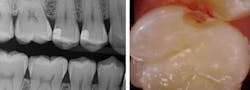

We derive our treatment decisions from various factors, including tooth surface, Canary Number, patient risk factors, and clinical judgment. The Canary Number is the score a tooth gets on the Canary Scale after being scanned (figure 1). Canary Numbers above 20 indicate decay. Previously, I would question if suspicious areas I observed in interproximal areas on digital radiographs were advanced enough to require restorations. On an interproximal surface, a Canary Number above 20 generally warrants a restoration.

Figure 1: The Canary Scale. Canary Numbers from 0–20 indicate healthy tooth structure, whereas a score of 21–70 indicates decay and a score of 71–100 indicates advanced decay.